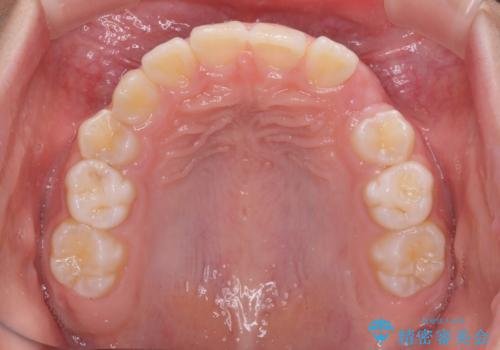

今後残っている乳歯が抜け、永久歯が萌出してくるため、調整可能なリンガルアーチを用いて保定を行っています。

12歳臼歯が萌出するまで経過観察を行い、すべての歯が萌出した後に、全顎矯正治療(Ⅱ期治療)を行っていきます。